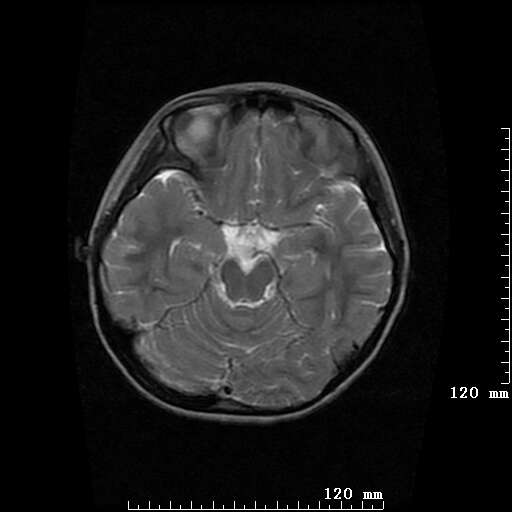

女,7岁,三岁才说话、走路。现智力尚可,走路不稳。临床怀疑大脑发育不全。

考虑 脑白质发育不良

脑折质变薄,双侧侧脑室稍扩张,支持考虑脑折质发育不良

侧脑室周围白质软化症。

考虑胼胝体发育不全,髓鞘形成不良。

支持考虑胼胝体发育不全,髓鞘形成不良。

脑裂畸形伴灰质异位

侧脑室周围白质数量减少,侧脑室不对称性扩大,左侧侧脑室后角呈方形改变,脑沟加深,结合临床考虑脑室周围白质软化症(pvl)。期待结果!

只看出灰质异位

支持脑白质发育不良。